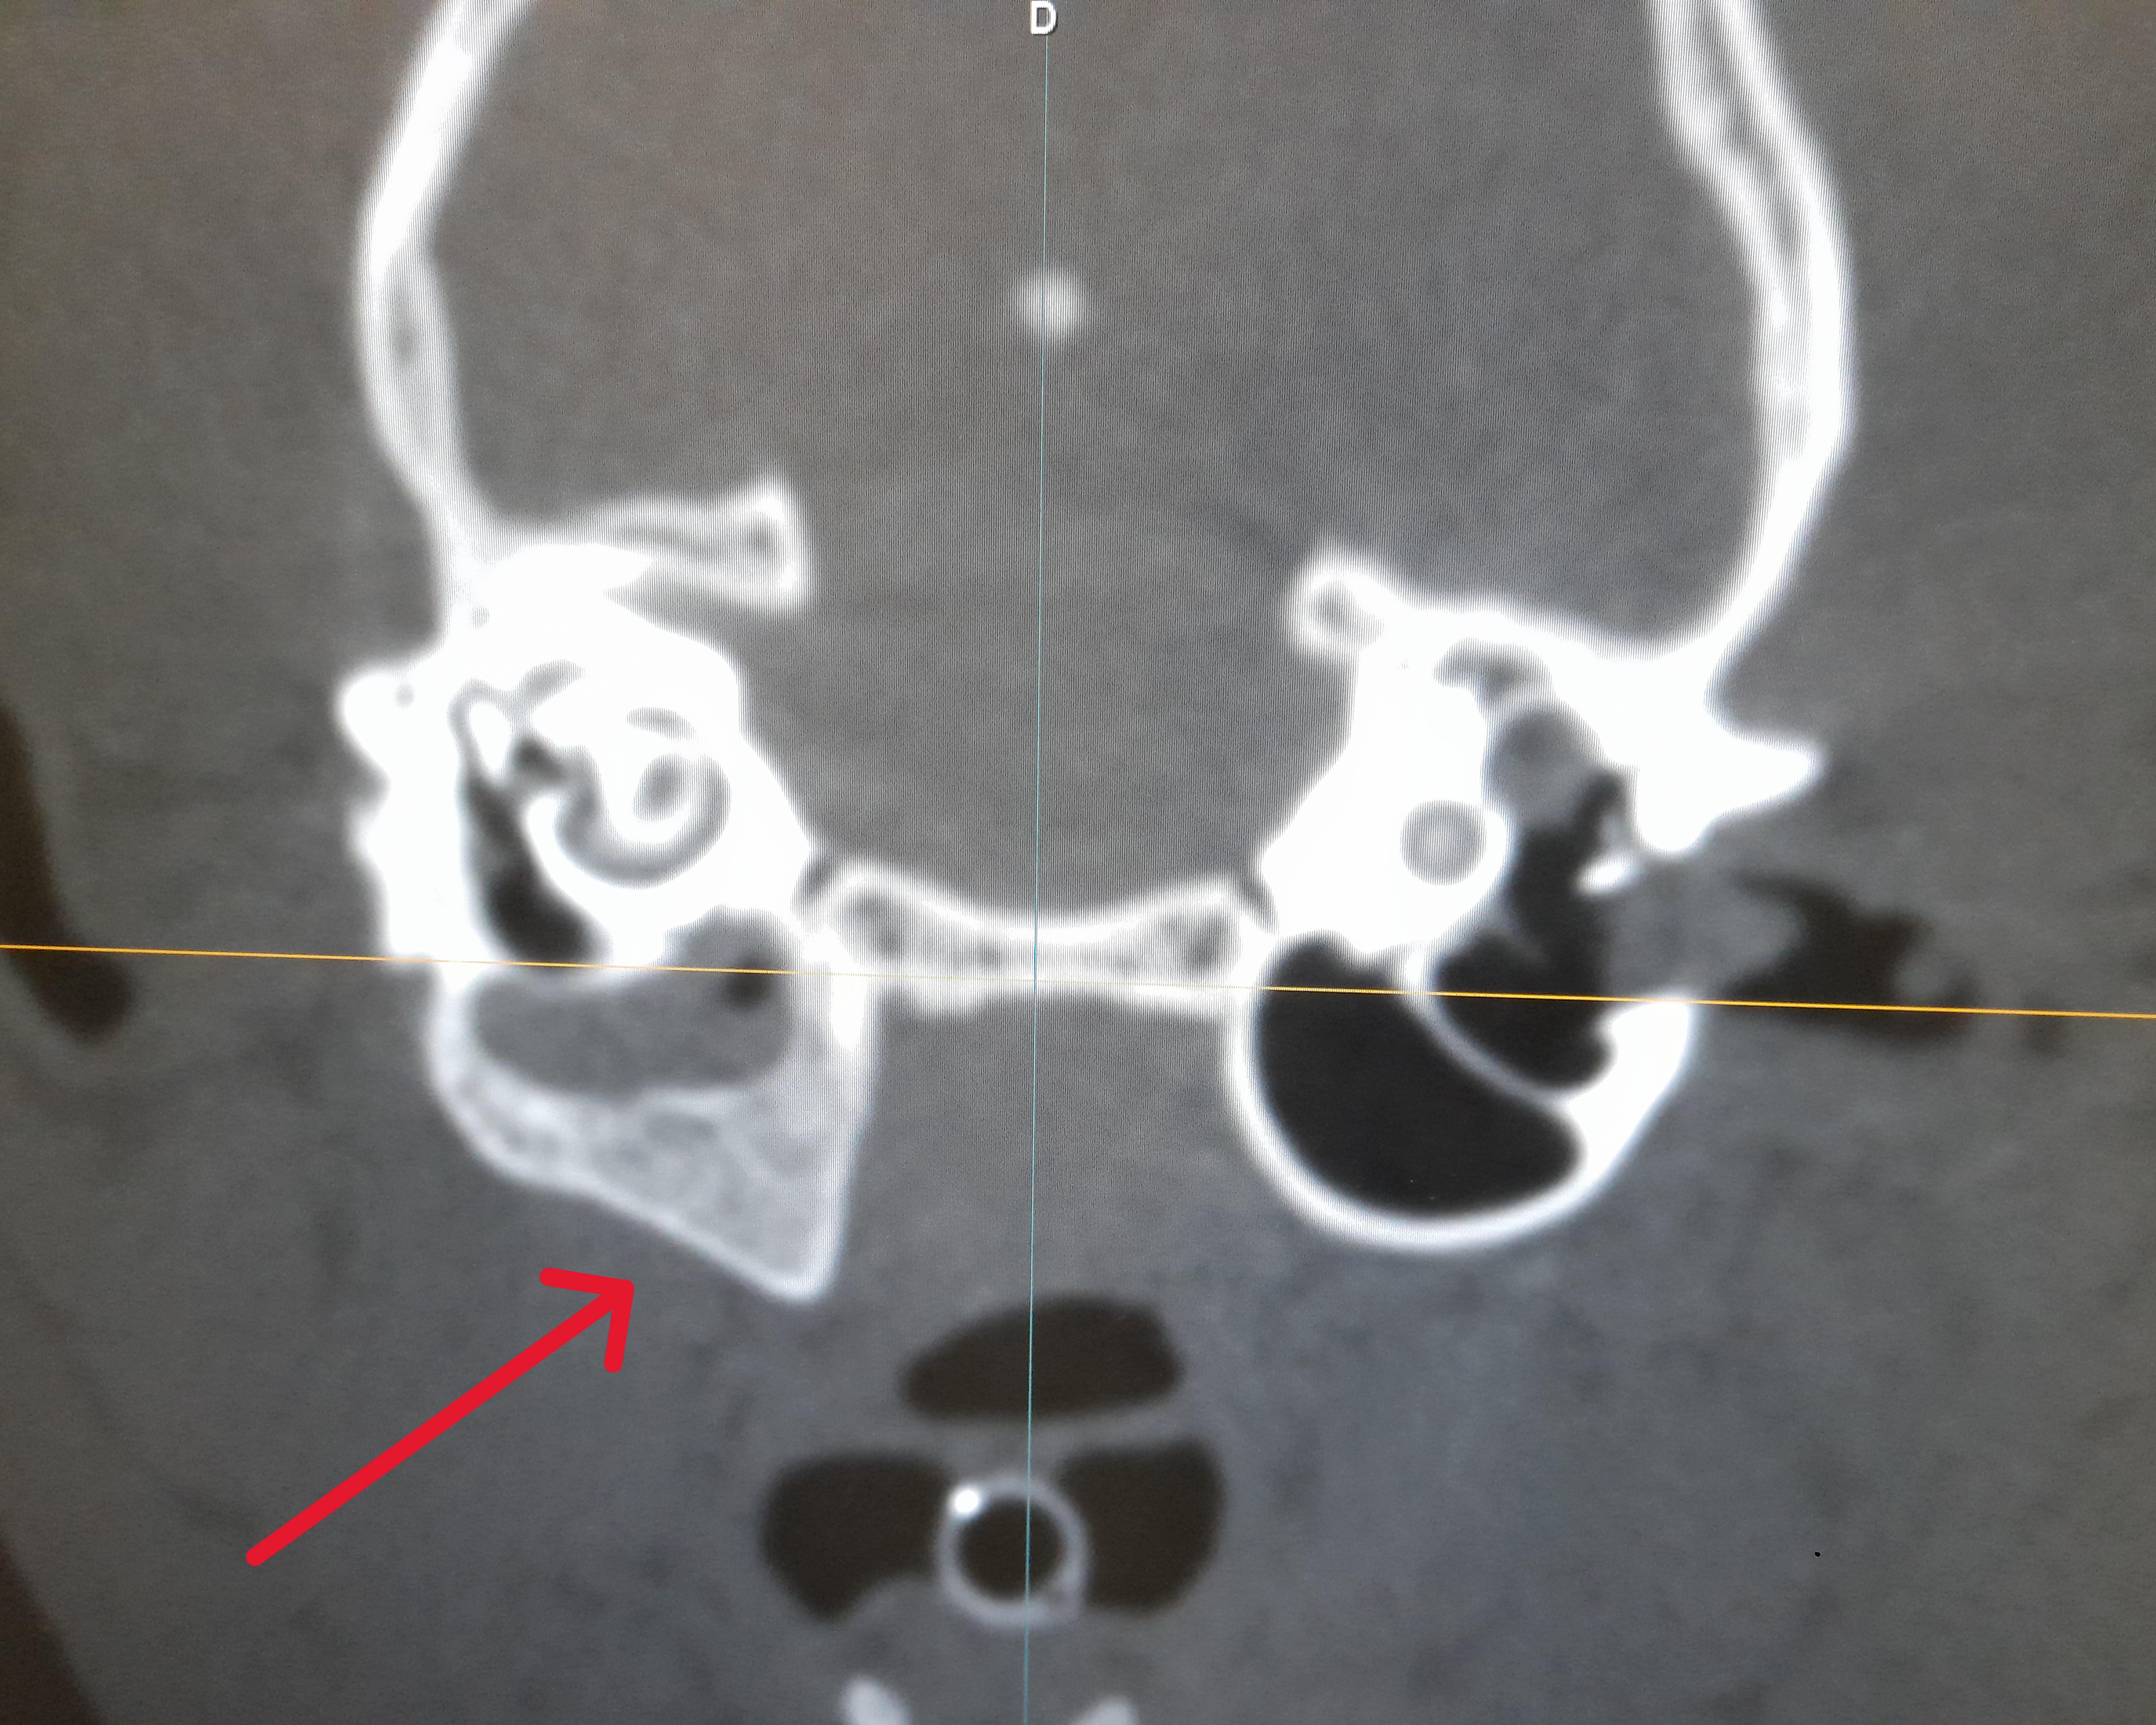

Kocourek byl dnes na CT vyšetření, které ukázalo, že má chronický zánět středního ucha. Zánět je viditelný na deformované kůstce, zřejmě jej trápí již několik let. Vše lze vyřešit operací, která je ovšem velmi nákladná (20-30 tis), tedy budeme rádi za každý příspěvek, který nám pomůže kocourkovi operaci zajistit.